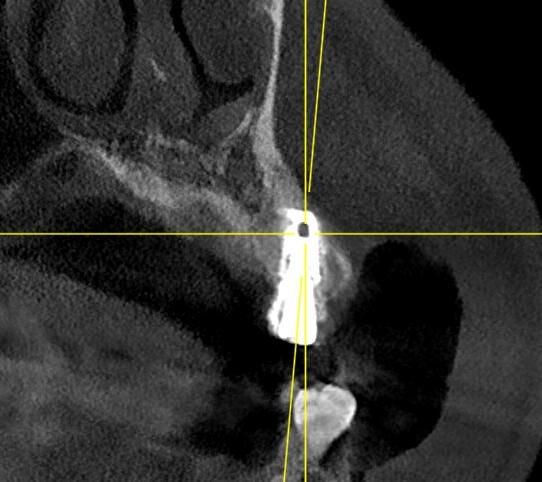

A proper implant journey starts with full records: 3D CBCT scans, X-rays, and clinical photos to evaluate bone, gums, and bite.

Successful implant surgery depends largely on the surgeon’s expertise. A skilled dentist ensures precise alignment and natural bite for lasting function. They handle complex cases with minimally invasive techniques for faster recovery and may offer same-day implant placement with a temporary crown. Using strict sterility and digital planning, they prioritize accuracy and your safety throughout.

Your implant journey starts with a detailed consultation, including photos, X-rays, and a 3D CBCT scan to assess bone and plan placement. Your dentist will discuss options, timelines, and any needed procedures like bone grafts. During surgery, a titanium implant is placed under local anesthesia, with sedation if needed, and a temporary tooth may be provided. Over 3 to 6 months, the implant fuses with your bone, creating a strong base. Once healed, an abutment is attached, and a custom crown or bridge is fitted for natural function and look. The process ends with aftercare instructions, bite checks, and regular reviews to ensure long-term success.